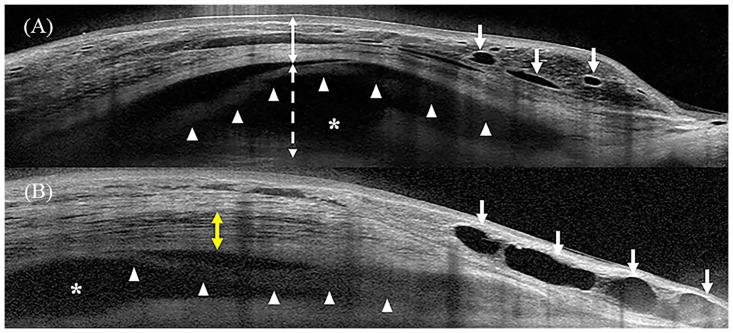

A total of 68 eyes of 68 patients with primary open-angle glaucoma who underwent trabeculectomy with AMT were included. Surgical success was defined as intraocular pressure (IOP) ≤ 18 mmHg and IOP reduction of ≥ 20% without medication on AS-OCT examination. Intrableb parameters, including bleb height, bleb wall thickness, striping layer thickness, bleb wall reflectivity, fluid-filled space score, fluid-filled space height, and microcyst formation were evaluated using AS-OCT. Logistic regression analysis was performed to determine factors associated with IOP control.

Of the 68 eyes, 56 eyes were assigned to the success group and 12 eyes to the failure group. In the success group, bleb height (P = 0.009), bleb wall thickness (P = 0.001), striping layer thickness (P = 0.001), fluid-filled space score (P = 0.001), and frequency of microcyst formation (P = 0.001) were greater than those in the failure group. Bleb wall reflectivity was higher in the failure group than in the success group (P < 0.001). In the univariate logistic regression analysis, previous cataract surgery was significantly associated with surgical failure (odds ratio = 5.769, P = 0.032).

A posteriorly extending fluid-filled space, tall bleb with low reflectivity, and thick striping layer were characteristics of successful filtering blebs after trabeculectomy with AMT.